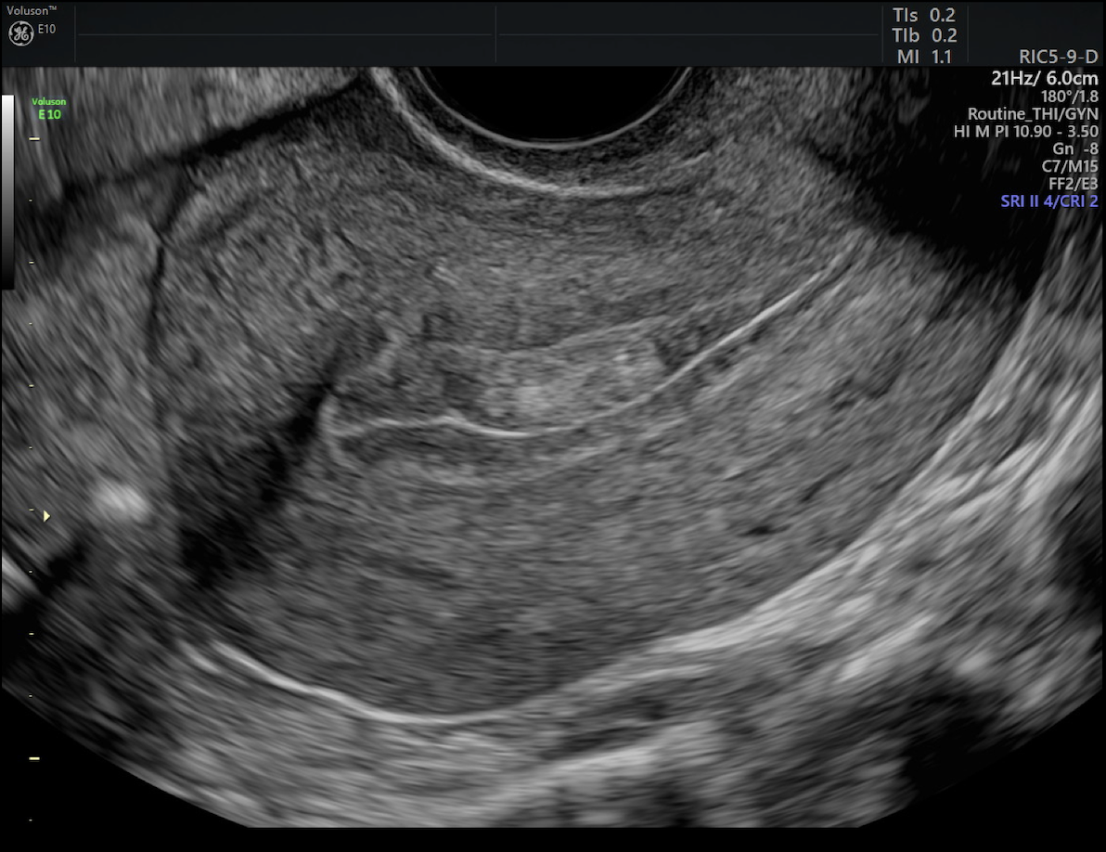

(A)

(B)

Imagem de ultrassom convencional mostrando pólipo (A), pólipo ao Doppler em cores (B) e ultrassom tridimensional VCI realçando o pólipo no endométrio (C).